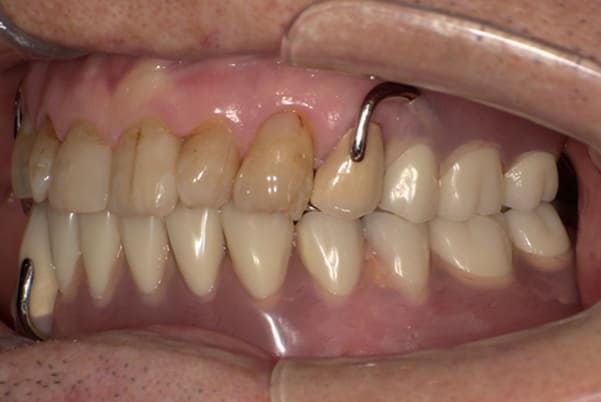

症例レポート[CASE.02]

- 男性(60代)

- 入れ歯がカパカパする、歯がぐらぐらして痛い、食いしばれない

- 上顎精密総金属床総入れ歯

- 下顎精密金属床部分入れ歯

上の前歯が重度歯周病により動揺し、残せない状態のため、入れ歯も動揺がありました。

ご自身の歯に負担の少ないバネ、また見た目も改善

バネをかける歯は繋げることで強度を増し、歯への負担を軽減し、歯の寿命を長くする設計へ。

バネがかかる歯の被せ物は、歯への負担を減らし、入れ歯が動きにくいようになる形態をあらかじめ付与することで、より入れ歯の機能が高まります。

治療を行う際、被せ物や入れ歯は、別々に考えるのではなく、一口腔単位としてお口全体のことを考え最良の治療計画を立てることが歯の寿命、機能効果を向上させるため、専門医としてこのことは常に心掛けて治療を行っています。

残りの歯に負担がかからないよう、被せ物と入れ歯の一体化を図った入れ歯

治療前は上下奥歯の入れ歯が削れていることで、かみ合わせが低くなり唇もつむった状態でした。

かみ合わせを適切な高さに戻したことで、本来の自然な口元へ。